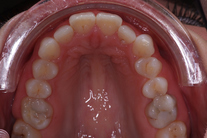

40-årig kvinna som tycker att de två framtänderna står ut framför alla andra tänder. Behandlingen bestod av 11 månader med genomskinliga Invisalignskenor.